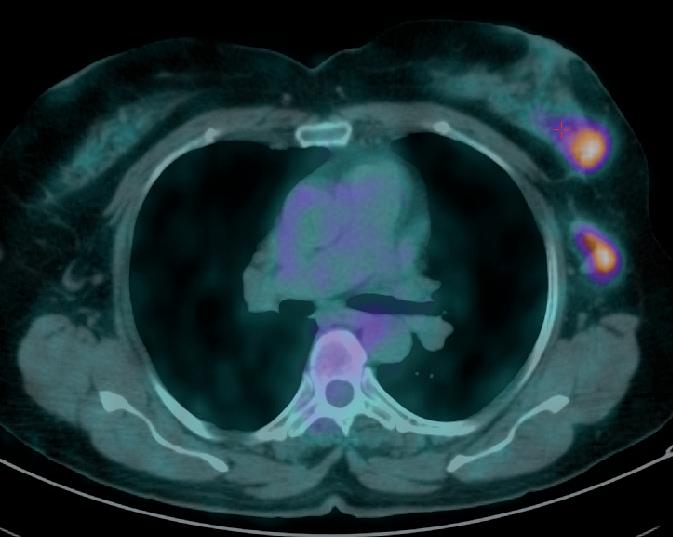

La PET (figura 1) metteva in evidenza la presenza di accumulo del tracciante metabolico in corrispondenza della formazione ovalare posta nel quadrante inferoesterno della mammella di sinistra (SUV massimo pari a 5,6). In in sede ascellare monolaterale, ulteriore grossolano linfonodo caratterizzato da analoga attività metabolica (SUV massimo pari a 5,1). Si segnalano inoltre, la presenza di alcune focalità di accumulo del tracciante metabolico di pertinenza scheletrica poste nel soma di D2, D11 e nell’emisacro di sinistra.

3 cicli di trattamento, alla PET di Febbraio 2019 (figura 2) si è dimostrata una sensibile regressione della lesione mammaria che presenta un SUV massimo pari a 2,9 vs 5,6 del precedente controllo; in sede ascellare di sinistra, apprezzabile sovracentimetrico linfonodo, modestamente captante il tracciante metabolico (SUV massimo pari a 1,7). Per quanto concerne le lesioni scheletriche descritte nel corso del precedente test, permane caratterizzato da modesta attività metabolica, esclusivamente un’unica lesione posta nel soma di D2. Non si risconoscono aree di accumulo di nuova comparsa.

1. PET Ottobre 2018.

2. PET dopo 3 cicli di ct con TXT trastuzumab e pertuzumab.